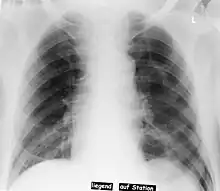

| Pneumothorax left sided | |

In radiology, the deep sulcus sign on a supine chest radiograph is an indirect indicator of a pneumothorax.[1][2] In a supine film, it appears as a deep, lucent, ipsilateral costophrenic angle[3] within the nondependent portions of the pleural space as opposed to the apex (of the lung) when the patient is upright. The costophrenic angle is abnormally deepened when the pleural air collects laterally, producing the deep sulcus sign.[4]

Patients with chronic obstructive pulmonary disease (COPD) may exhibit deepened lateral costophrenic angles due to hyperinflation of the lungs and cause a false deep sulcus sign.[4]